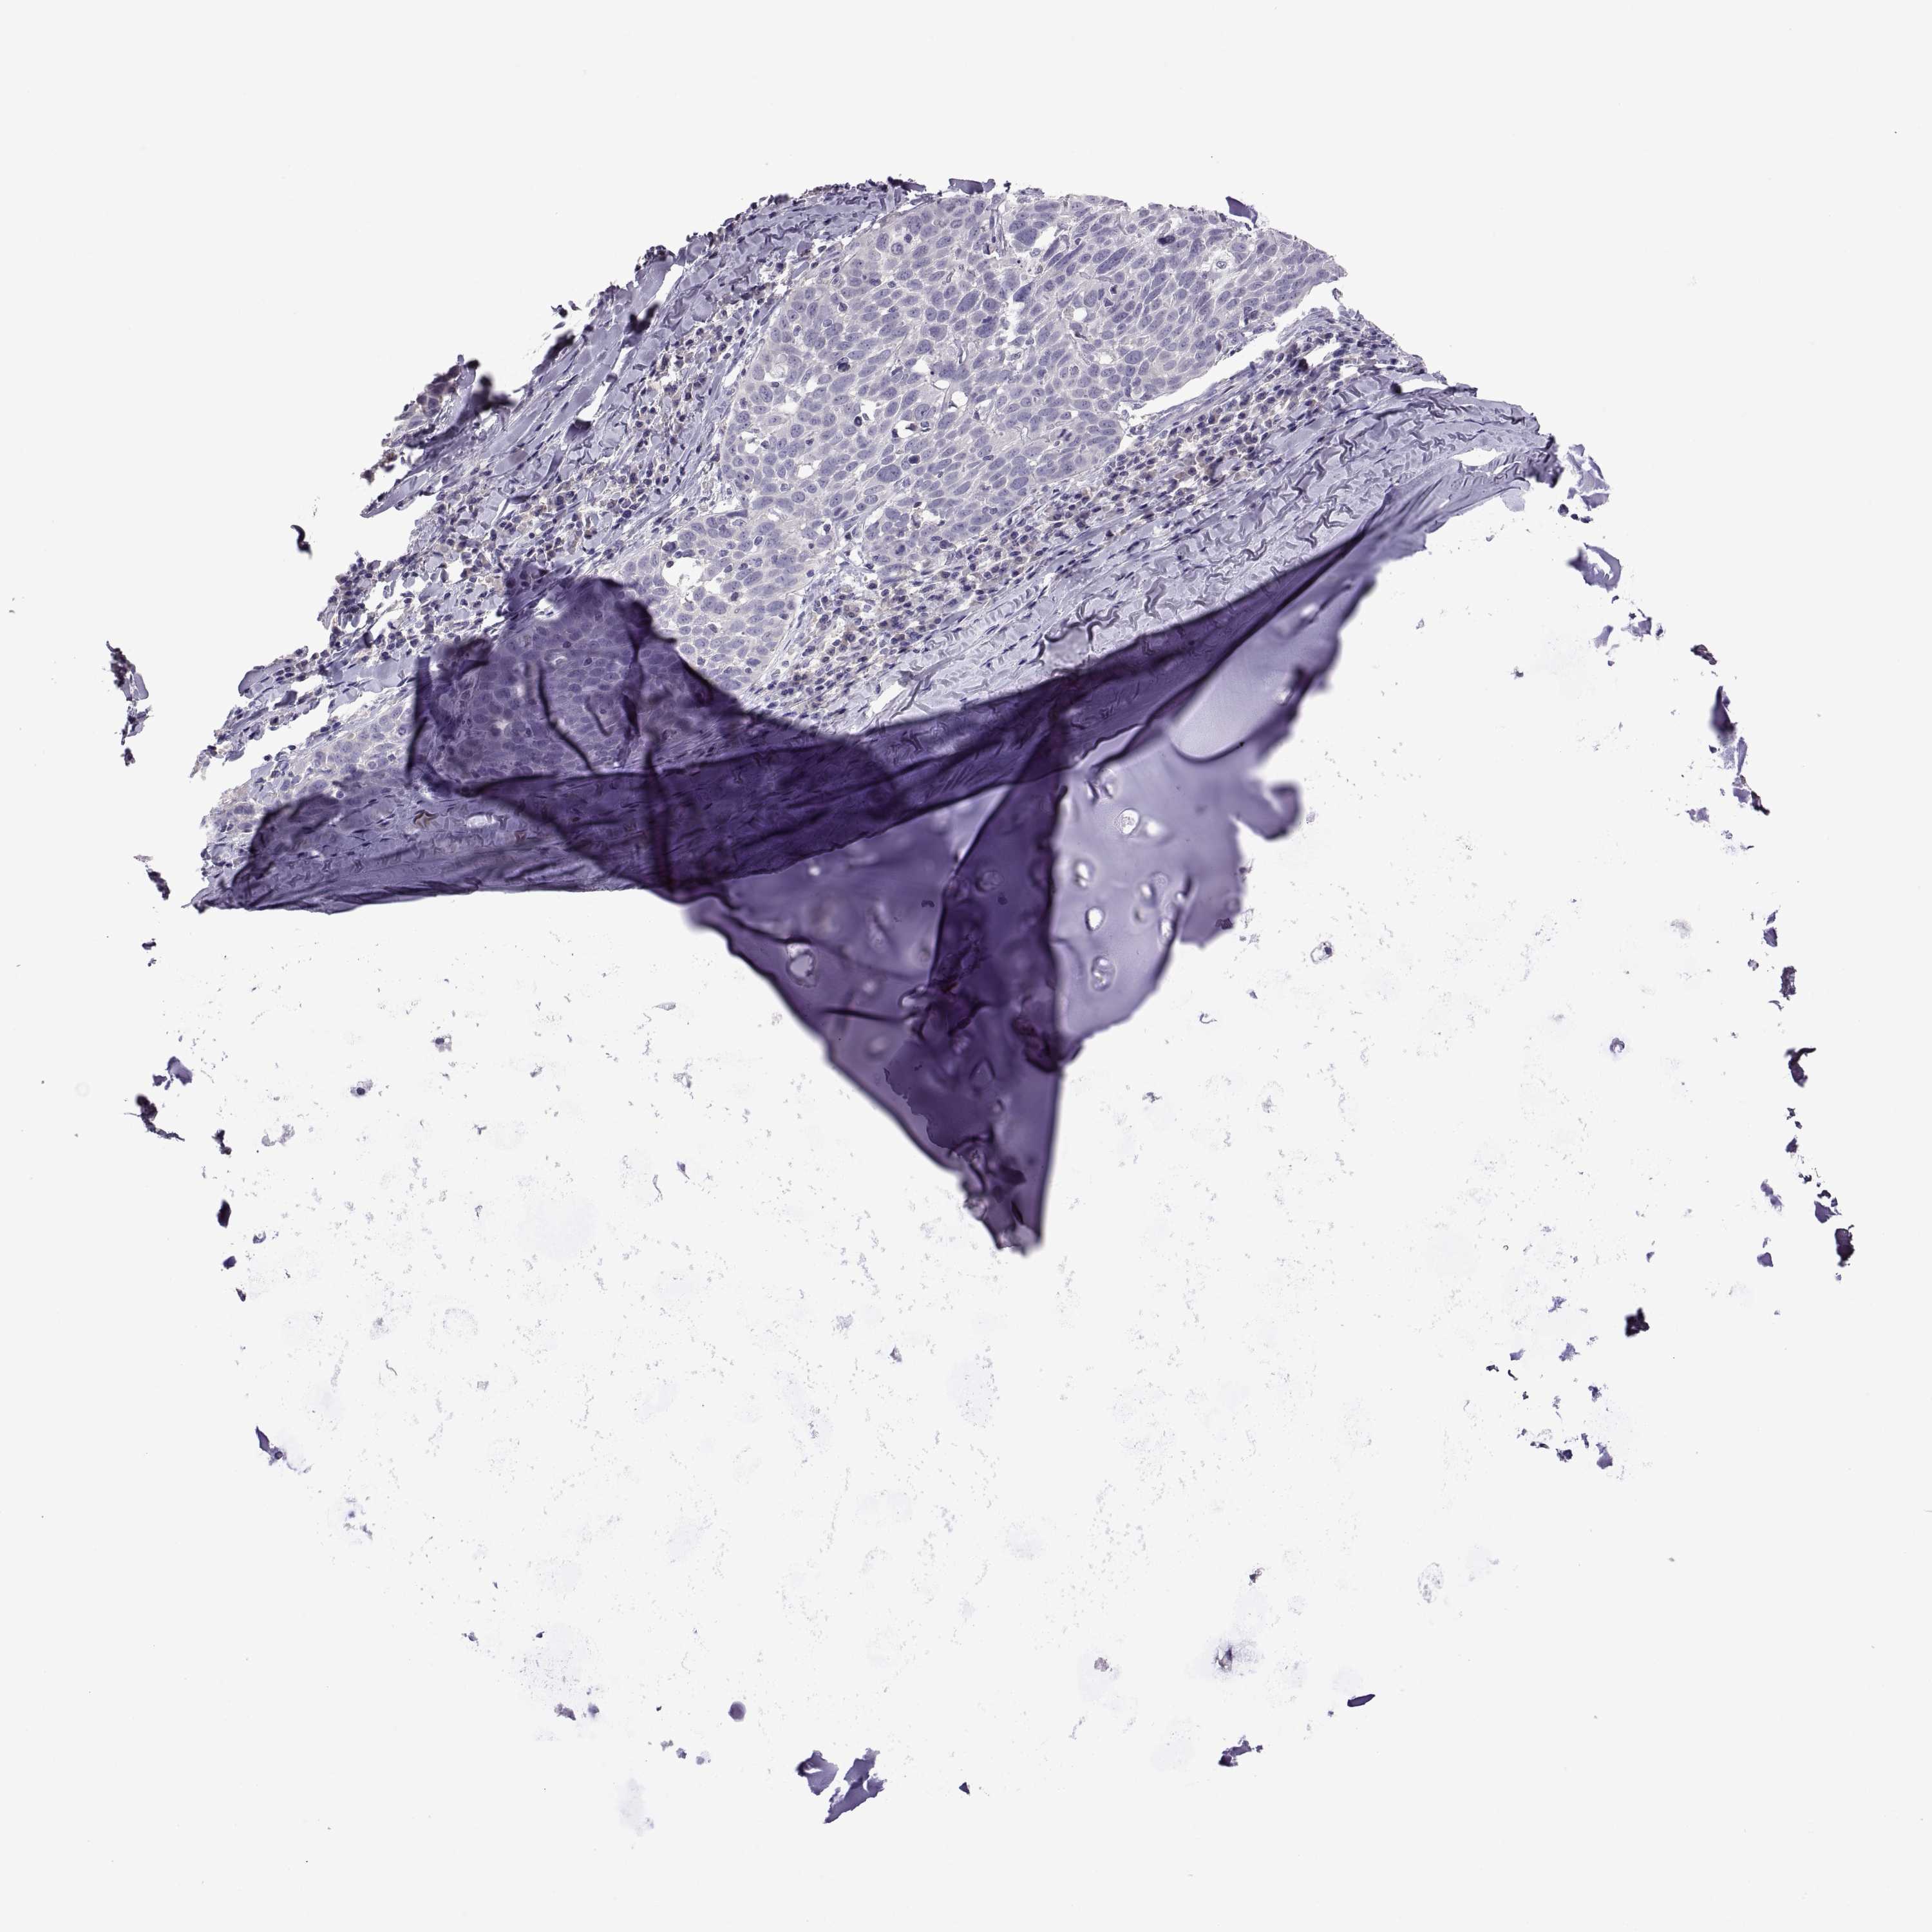

LUNG ADENOCARCINOMA (VALIDATION) - Interactive survival scatter ploti

The Survival Scatter plot shows the clinical status (i.e. dead or alive) for all individuals in the patient cohort, based on the same data that underlies the corresponding Kaplan-Meier plots. Patients that are alive at last time for follow-up are shown in blue and patients who have died during the study are shown in red.

The x-axis shows the expression levels (FPKM) of the investigated gene in the tumor tissue at the time of diagnosis. The y-axis shows the follow-up time after diagnosis (years). Both axes are complimented with kernel density curves demonstrating the data density over the axes. The top density plot shows the expression levels (FPKM) distribution among dead (red) and alive patients (blue). The right density plot shows the data density of the survived years of dead patients with high and low expression levels respectively, stratified using the cutoff indicated by the vertical dashed line through the Survival Scatter plot. This cutoff is automatically defined based on the FPKM cutoff that minimizes the p-score. The cutoff can be changed by dragging the vertical line or by entering a cutoff value in the square labeled "Current cut-off".

Under the Survival Scatter plot the p-score landscape (black curve; left axis) is shown together with dead median separation (red curve; right axis). Dead median separation is the difference in median mRNA expression between patients who have died with high and low expression, respectively. It is calculated as follows: median FPKM expression of dead patients with high expression - median FPKM expression of dead patients with low expression. This is intended to aid the user in visually exploring custom cutoffs and the associated p-scores and dead median separation.

Individual patient data is displayed and can be filtered by clicking on one or more of the category buttons on the top of the page. Categories describing expression level and patient information include: high, low, alive, dead, female, male and tumor stages. The scale of the x-axis can be toggled between linear and log-scale by clicking on the "x log" button. Mouse-over function shows TCGA ID, patient information and mRNA expression (FPKM) for each patient.

& Survival analysisi

Kaplan-Meier plots summarize results from analysis of correlation between mRNA expression level and patient survival. Patients were divided based on level of expression into one of the two groups "low" (under cut off) or "high" (over cut off). X-axis shows time for survival (years) and y-axis shows the probability of survival, where 1.0 corresponds to 100 percent.

TBX19 is not prognostic in Lung Adenocarcinoma (validation)

Best expression cut offi

Based on the FPKM value of each gene, patients were classified into two groups and association between prognosis (survival) and gene expression (FPKM) was examined. The best expression cut-off refers the FPKM value that yields maximal difference with regard to survival between the two groups at the lowest log-rank P-value. Best expression cut-off was selected based on survival analysis .

When clicking on this number, the vertical dashed line indicating cut-off, the interactive survival plot, and the Kaplan-Meier curve will be adjusted to show results based on the best expression cut-off.

: 1.96

TCGA RNA samplesi

RNA-seq data is reported as average FPKM (number Fragments Per Kilobase of exon per Million reads), generated by the The Cancer Genome Atlas (TCGA) .

Normal distribution across the dataset is visualized with box plots, shown as median and 25th and 75th percentiles. Points are displayed as outliers if they are above or below 1.5 times the interquartile range. FPKM values of the individual samples are presented next to the box plot.

Average pTPM 1.9

Number of samples 105